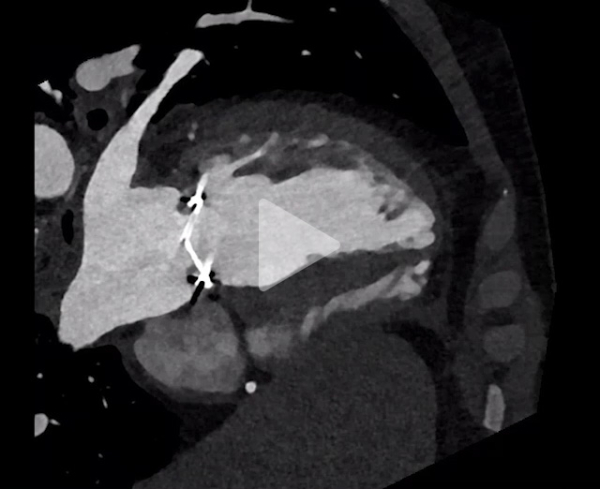

Scanner cardiaque

- Persistance du thrombus (discrète diminution) et blocage de l’ailette

- Absence d'élément de l'appareil sous valvulaire gênant la mobilité

- Bon fonctionnement de la prothèse aortique mécanique

La bonne réponse était la C : Thrombolyse : selon l'ultra slow protocole de Ozkan et al (25mg/24h à répéter jusqu'à 8 fois ; intervalle libre de 6h entre chaque cycle avec relais par HNF; avec évaluation par ETT+/-ETO entre chaque dose). Scanner cérébral normal.